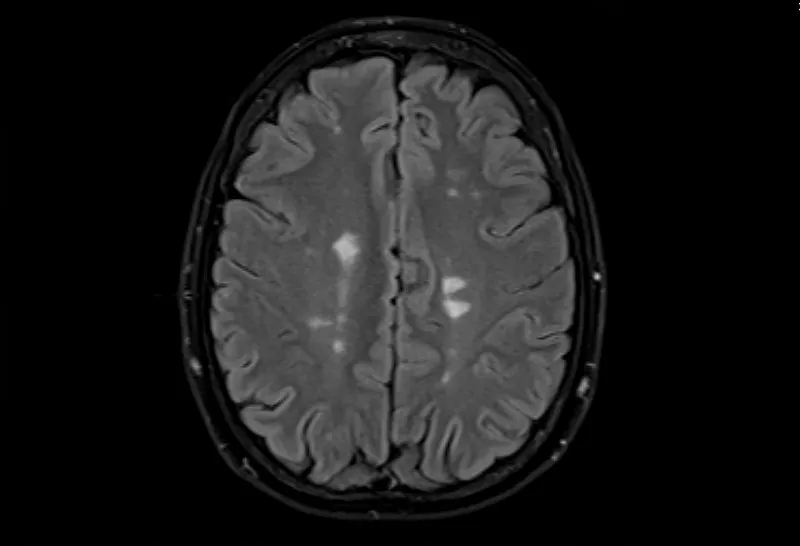

- 大腦的MRI掃描可以顯示損傷區(qū)域,但沒有單一的測(cè)試可以診斷MS。

測(cè)試的組合用于診斷MS。最好的測(cè)試是對(duì)您的大腦和脊髓進(jìn)行核磁共振檢查,以檢測(cè)損傷區(qū)域。您可能還需要進(jìn)行血液檢查、腰椎穿刺和測(cè)量神經(jīng)活動(dòng)的測(cè)試。

很難做出診斷,因?yàn)闆]有針對(duì)MS的單一測(cè)試。如果有證據(jù)表明您的中樞神經(jīng)系統(tǒng)的不同部位在不同時(shí)間受損,除了MS之外別無(wú)其他解釋,您將被診斷為MS。